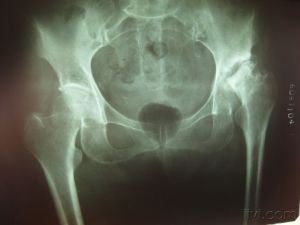

早期股骨頭壞死實體 股骨頭壞死亦稱股骨頭無菌性壞死和股骨頭缺血性壞死,它是骨傷科臨床常見而又難治的慢性疾病之一,股骨頭壞死是由於髖部外傷,長期套用激素類藥物,酒精中毒等原因,引起股骨頭血液供應障礙,股骨頭骨組織不能得到正常的營養,使股骨頭組織中的骨細胞,骨髓造血細胞,脂肪細胞發生壞死。由於壞死的骨組織脆弱,加之髖關節需要負重,日久就會發生股骨頭塌陷,影響全部髖關節。各期症狀表現如下:

早期症狀有:腰痛,患側臀部疼痛,患側腹股溝疼痛,患肢膝關節疼痛,患肢畏寒,活動多時無力,酸痛,易疲勞。這些症狀不能同時出現,有人出現一二個症狀或幾個症狀,短時間出現後就消失,反覆多次。這就是股骨頭壞死的早期症狀,應及時到醫院作CT,ECT或核磁共振檢查,都能發現股骨頭壞死。拍X片是不能夠早期診斷的。當X片出現改變時, 病情已經達到中晚期了,治療有些晚了。因為早起股骨頭壞死X片只能看到股骨頭周圍血液循環減低,骨質疏鬆,少量囊狀改變。所以僅憑X片一般不能早期發現。而此時因股骨頭內壓增高,患肢各部位疼痛比較明顯,經常被誤診為風濕病腰椎病膝關節病等,治療止痛,常用一些止痛藥或封閉等療法,症狀消失,即認為病癒了,造成誤診誤治,使病情發展到中晚期,從而耽誤了患者的最佳治療時機。

中期股骨頭壞死,症狀非常明顯,主要有跛行、行走疼痛、功能發生障礙,拍X片時,會看到骨小梁大部分消失,囊狀改變,骨質硬化,股骨頭軟骨斷裂塌陷。

晚期股骨頭壞死,患者跛行更加嚴重,明顯感到腿短,行走困難,疼痛,X片會看到股骨頭扁平,塌陷,關節間隙狹窄或消失,囊狀改變明顯,骨質硬化面積較大,股骨頭軟骨完全斷裂,關節面粗糙。

⑤X線表現。骨紋理細小或中斷,股骨頭囊腫、硬化、扁平或塌陷。

股骨頭壞死 股骨頭壞死最先出現的自覺症狀就是疼痛,疼痛的部位是髖關節周圍、大腿內側、前側或膝部。早期 疼痛開始為隱痛、鈍痛、間歇痛,活動多了疼痛加重,休息可以緩解或減輕。但也有呈持續性疼痛的,不 管是勞累還是休息,甚至躺在床上也痛。而且,疼痛逐漸加重。此時在X線上雖然沒有明顯的形態異常改 變,但是髖關節已有不同程度的功能受限。比如病人患側髖關節外展、鏇轉受限,下蹲不到位等等。股骨頭壞死到了晚期,股骨頭塌陷、碎裂、變形,有的可造成髖關節半脫位,此時的疼痛與髖關節活動、負重有直接關係。活動時關節內因骨性磨擦而疼痛,靜止時頭臼之間不發生磨擦,疼痛也就不明顯了。所以說, 行走、活動疼痛加重,動則即痛,靜則痛止或減輕。總之,早期是以疼痛為主,伴有功能受限;晚期以功能障礙為主,伴有疼痛。

X光片顯示股骨頭的承載系統中的骨小梁結構排列紊亂、斷裂,出現股骨頭邊緣毛糙,臨床上伴有或不伴有局限性輕微疼痛。

X光片顯示股骨頭內部會出現小的囊變影,囊變區周圍的環區密度不均。骨小梁結構紊亂、稀疏或模糊。也可出現細小的塌陷,塌陷面 積可在10-30%臨床伴有疼痛明顯、活動輕微受限等。

X光片顯示股骨頭形態改變,可出現邊緣不完整、蟲蝕狀或扁平等形狀,骨小梁部分結構消失,骨密度很不均勻,髖臼及股骨頭間隙增寬或變窄,也可有骨贅骨的形成,臨床表現疼痛、間歇性的跛行、關節活動受限、患肢有不同程度的縮短等。

股骨頭的形態、結構明顯改變,出現大面積不規則塌陷或變平,骨小梁結構變異。髖臼與股骨頭間隙消失等。臨床表現為疼痛、功能障礙、僵直不能行走,出現脫位或半脫位,牽涉膝關節功能活動受限。